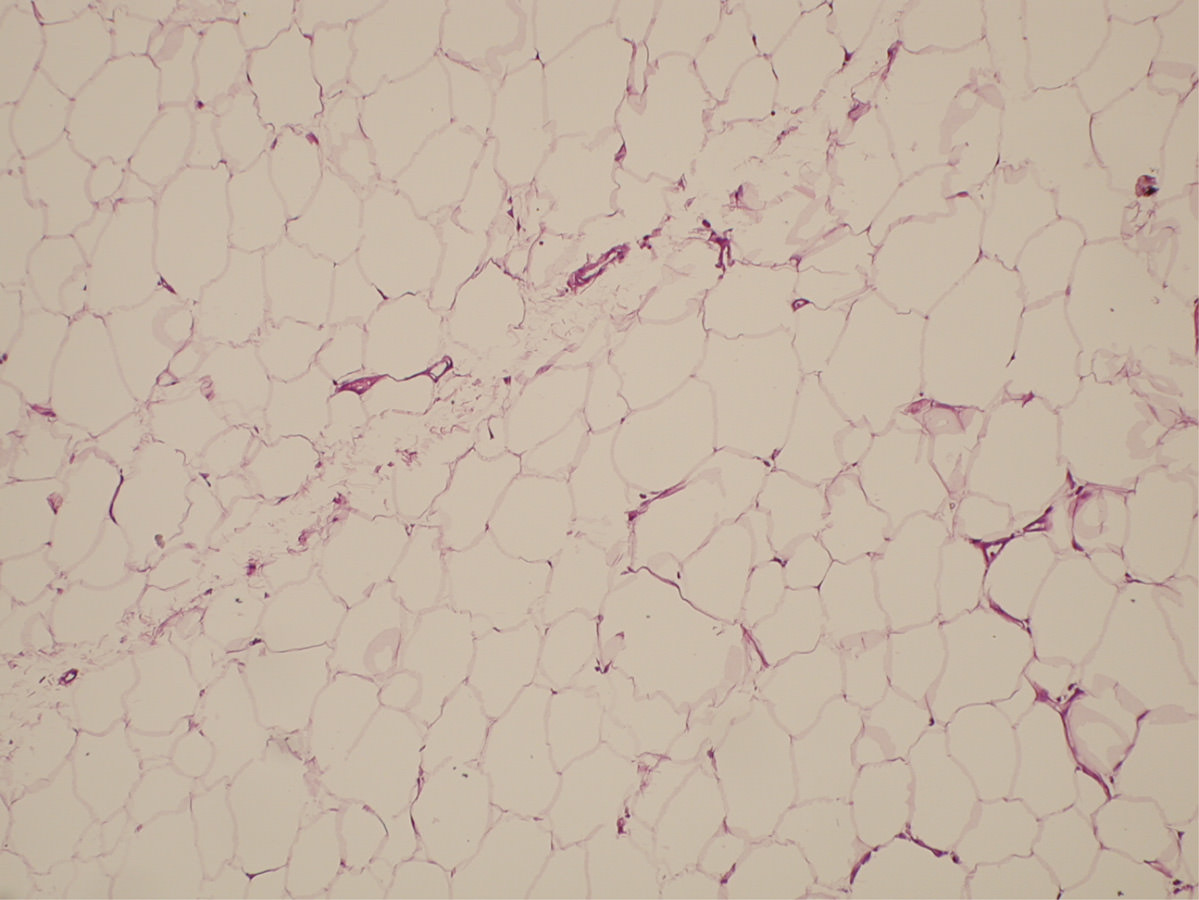

Para realizar un correcto tratamiento es necesario identificar la etiología y, solo en caso de no tener un diagnóstico de certeza, vamos a reconocer la artrofibrosis como causa de la rigidez, como un proceso de metaplasia del fibrocartílago con incremento de la fibrosis intersticial(13)(14)(Figuras 2 y 3). La historia clínica ayuda a pensar en los problemas de cicatrización, la presencia de infección superficial en el postoperatorio inmediato, los traumatismos y en la aparición de una rigidez(15)(16). Un cuadro que aparece en el postoperatorio inmediato lleva a pensar que se trata de un error quirúrgico o una rehabilitación inadecuada, mientras que en el caso de una rigidez de aparición tardía, tras un periodo de movilidad satisfactoria, nos encaminará a un proceso de infección latente o descementación.

Figura 2. Patrón intersticial normal de la grasa de Hoffa.